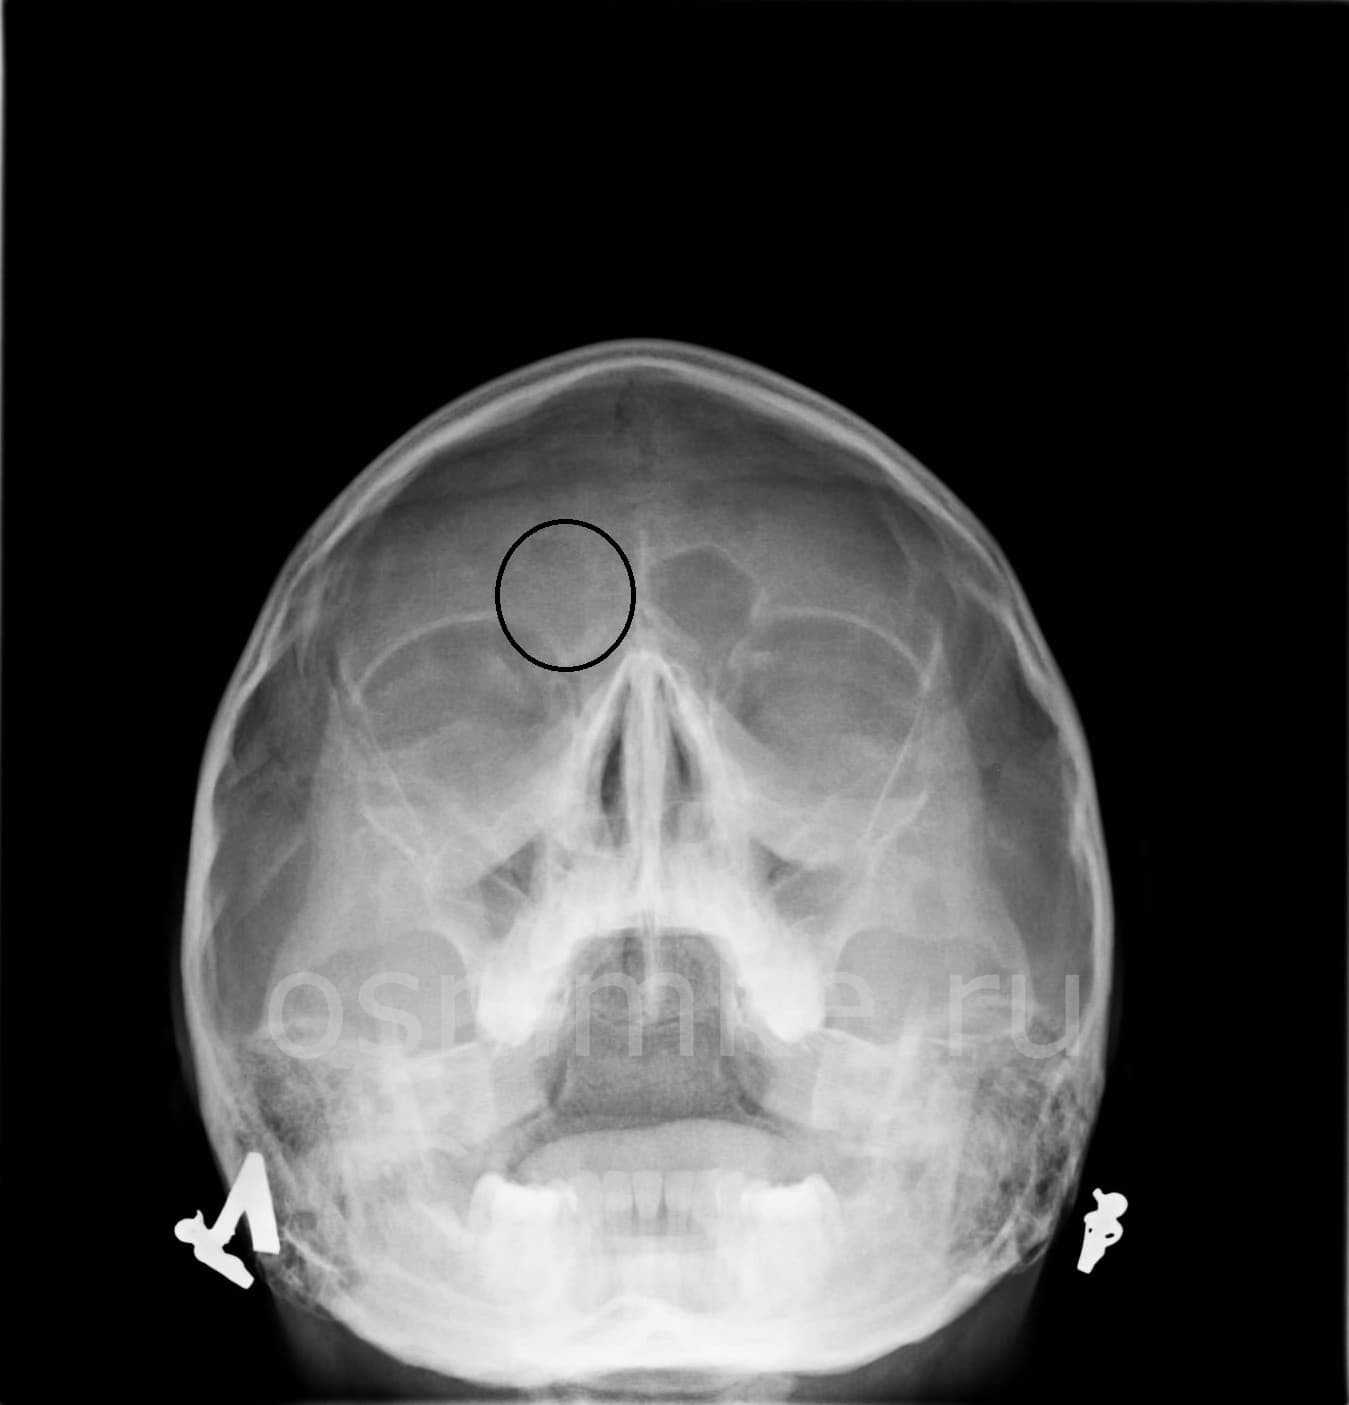

На рентгенограмме придаточных пазух носа в носо-подбородочной проекции визуализируется носовая полость, глазницы, верхнечелюстные, лобные и решетчатая пазухи.

На рентгенограмме околоносовых пазух видны такие анатомические элементы:

- Носовая полость в виде просветления треугольной формы, разделенного перегородкой на симметричные половины.

- В каждой половине носовой полости видны тени носовых раковин, а между ними – просветления, соответствующие носовым ходам.

- С обеих сторон от носовой полости видны треугольные просветления с четкими границами – верхнечелюстные пазухи.

- В пространстве между глазницами видна полость решетчатой пазухи, разделенная тонкими стенками на несколько клеток.

- Над глазницами в глубине кости определяются лобные пазухи, они могут иметь разную форму, иногда их разделяют костные перегородки.

Любые отклонения от нормальной картины оцениваются врачом-рентгенологом и отражаются в заключении. Результат исследования не является диагнозом. Он оценивается ЛОР-врачом в совокупности с другими признаками возможного заболевания.

При заболеваниях пазух врач рентгенолог может обнаружить:

- Признаки острого воспаления: слизистая утолщена, в полости пазухи виден горизонтальный уровень жидкости, при нагноении граница содержимого может располагаться косо или быть вогнутой, однако это не обязательный признак;

- Признаки хронического воспаления: значительное утолщение стенок, сужение просвета пазухи вплоть до его полного исчезновения (отсутствия пневматизации).

- Признаки травмы: переломы костных стенок, наличие свободных плотных фрагментов в пазухе, смещение отломков.

- Признаки опухоли: объемное образование в полости, имеющее повышенную плотность.

- Признаки кисты: округлое просветление за пределами нормальной границы пазухи.